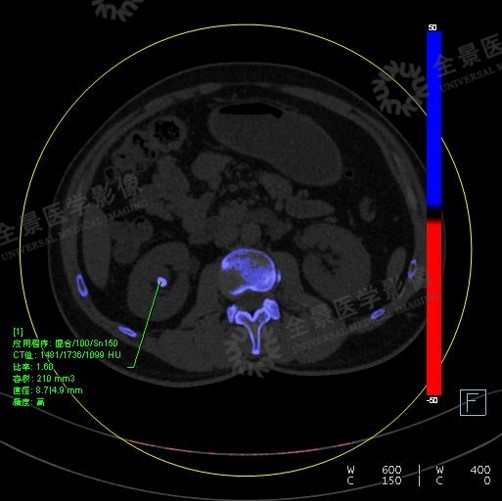

后处理结果会显示肾结石的一些参数,如高低能量下的CT值,比率,结石的体积,直径以及评估的精度:

将肾结石处理参数中的最小值适当降低,那些低密度的小结石也会加上伪彩,从而可以评估结石的成分。

结石双能量分析(100kv/150kv)示:双肾肾盂内多发结石,均标记为蓝色。左肾数枚小结石呈颗粒状,大者大小约2.6mm×2.3mm,体积13.9mm3,CT比值1.53(双能量指数)。右肾数枚结石,大者大小约8.7mm×4.9mm,体积210mm3,CT比值1.6(双能量指数)。

双能量结石成分分析为双肾多发羟磷灰石成分结石,非尿酸结石。